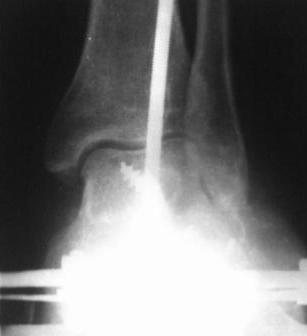

|

На счет того ,что при плоскостопии не наступает артроз голеностопного сустава-

Выдержка из статьи по адресу

E:\eMedicine - Pes Planus Article by Matthew Buchanan.mht

"In 1997, Myerson added a fourth stage to Johnson and Strom's original description of PTT dysfunction.10 Long-standing hindfoot valgus places increasing stress on the deltoid complex, with eventual loss of competence. The resultant valgus tilt of the talus leads to eccentric loading of the ankle with subsequent tibiotalar arthrosis"

С уважением, Анатолий Баранецкий, Москва.

4 стадия плосковальгусной стопы.jpg